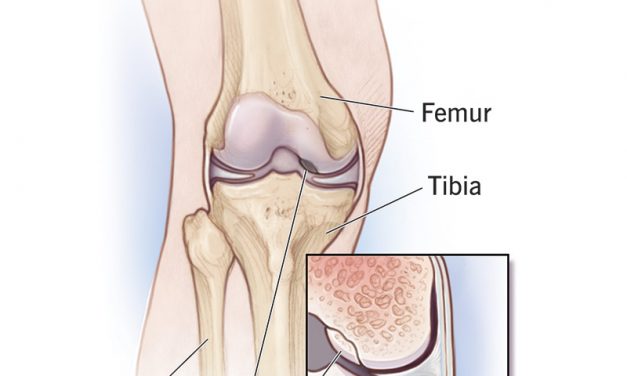

by Kimberly Allen, RN Osteochondritis dissecans or OCD is a relatively rare condition that affects...

by Kimberly Allen, RN Though it is one of the most commonly diagnosed diseases causing knee pain...